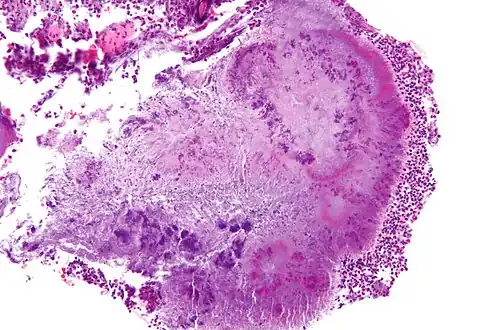

Micrograph of actinomycosis, H&E stain

Micrograph of actinomycosis, H&E stain Micrograph of actinomycosis, GMS stain